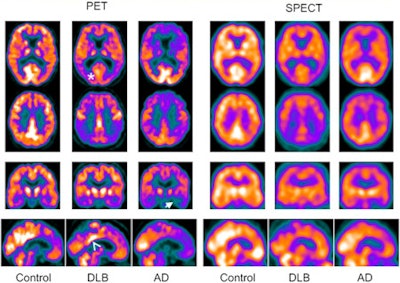

The FDG-PET and SPECT results were rated visually by three medical physicists who were blinded to diagnoses and clinical information. The images were rated for quality in several areas of the brain associated with Alzheimer's and dementia with Lewy bodies.

The physicists assessed radiopharmaceutical uptake in the precuneus and lateral parietal lobes in the Alzheimer's patients and those with dementia with Lewy bodies, in addition to the posterior cingulate in patients with dementia with Lewy bodies.

Among the patients with dementia, the researchers examined the ability of FDG-PET and SEPCT to differentiate between Alzheimer's and Lewy body dementia. In this analysis, FDG-PET had 58 correct diagnoses, while SPECT had 48 correct diagnoses. FDG-PET showed 74% sensitivity for Alzheimer's, compared with 54% for SPECT. FDG-PET's specificity was 70%, compared with 67% for SPECT.

"There was a tendency for scan results correctly classified as dementia on F-18 FDG PET to be called normal on SPECT, and SPECT seemed to have better performance for dementia with Lewy bodies, with most Alzheimer's SPECT scans being rated unclear," the authors noted.